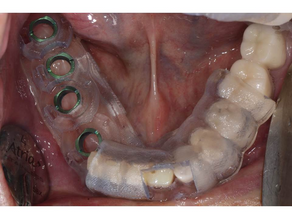

Various Implants Placement using Neo NaviGuide System

Case 1 Implant Placement using the Neo NaviGuide in the maxillary 2dn Premolar Area Pre-operative photograph Surgical Report Surgical...